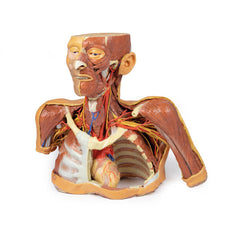

The models are very detailed and delicate. With normal production machines you cannot realize such details like shown in these models.

The printer used is a color-plastic printer. This is the most suitable printer for these models.

The plastic material is already the best and most suitable material for these prints. (The other option would be a kind of gypsum, but this is way more fragile. You even cannot get them out of the printer without breaking them).The huge advantage of the prints is that they are very realistic as the data is coming from real human specimen. Nothing is shaped or stylized.

The users have to handle these prints with utmost care. They are not made for touching or bending any thin nerves, arteries, vessels etc. The 3D printed models should sit on a table and just rotated at the table.